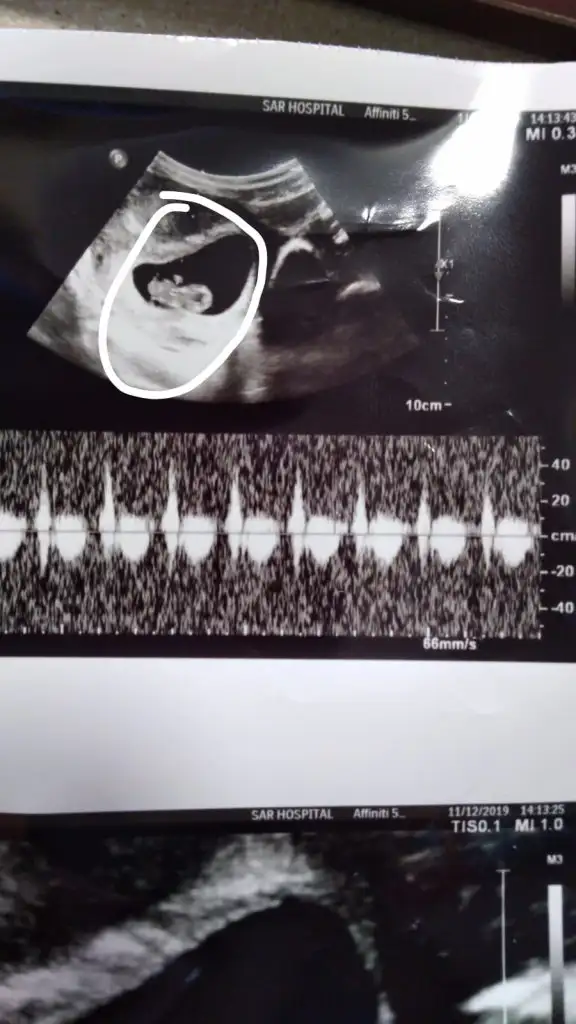

13 haftalik burada 16 da gelin dedi doktorum. bakalim tesekkur ederim cok cokKaç haftalık sanki kız gibi ama 11+ yada 12+ olmalı usg buyuk görünüyor gibi 13+ sonrası organ tamamlanmış oluyortam emin değilim tahminimden kız gibi gibi diyorum

İlk usgdeki nubu tam dik degil yakınlaştırınca bozuluyor foto digerleri net değil başka varsa tahmin ederim tam dik degil paralelde değil kafa yapısınıda ekledim kızda karar verdim aslında kızda olmayada bilir

6+6 karından bakıldıysa kız vajinal bakıldıysa erkek digeri kaç hafta yazmıyor

Karindan bakildi o da 8 haftalik6+6 karından bakıldıysa kız vajinal bakıldıysa erkek digeri kaç hafta yazmıyor